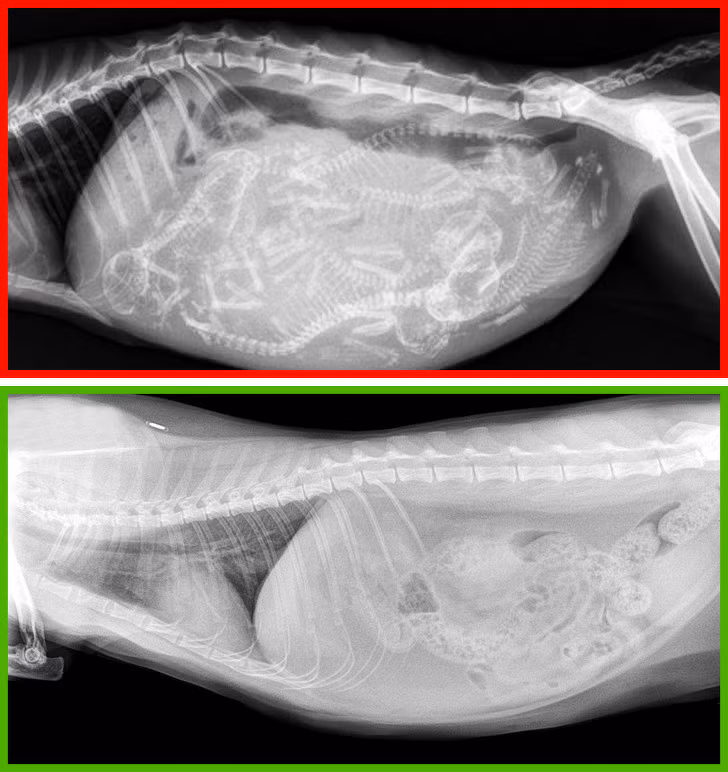

10. Không triệt sản

Trong hầu hết các trường hợp, triệt sản có tác động tích cực đến sức khỏe của mèo. Ngoài làm giảm nguy cơ gây ra các khối u ở hệ sinh sản, triệt sản khiến mèo thuần tính hơn và tránh trường hợp mèo trốn nhà đi chơi.